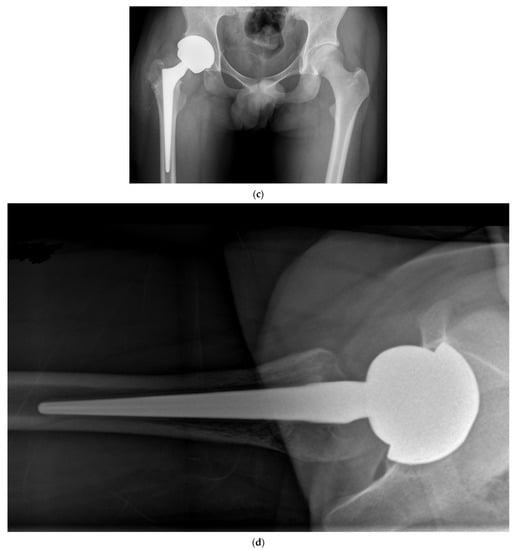

Figure 4.

Anteroposterior pelvis radiograph of a patient complaining of right hip pain. Compared to his native left hip, the right 28 mm THA center of rotation was elevated, the femoral offset was increased, and leg length was shortened.

We prefer to use a fixed neck stem with three different neck angle options to better meet the different patients’ anatomies rather than a stem design with a unique angle and two different offsets (standard/lateralized). Less influenced by the risk of instability, surgeons using LDH THA can better optimize a patient’s leg length and femoral offset (Figure 5). In our experience and the literature, up to 10 mm of leg length difference can be tolerated; a shorter leg is much better tolerated than a longer one by patients []. In the cases where we hesitate between a shorter or a longer head (example: 0 mm vs. a +4 mm), we, therefore, select the shorter one.

Figure 5.

(a) Antero-posterior pelvis radiograph of a 55-year-old man with a right metal-on-metal 28 mm THA and severe osteoarthritis of the left hip. (b) Postoperative radiograph after a left LDH THA with leg length and femoral offset restoration.